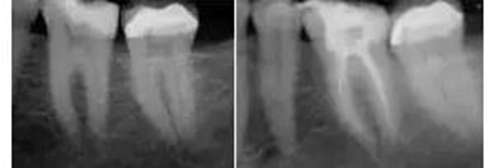

工作尖僅被置于開(kāi)髓洞形的冠方。當(dāng)沖洗液占據(jù)整個(gè)根管系統(tǒng),開(kāi)啟設(shè)備后震蕩波向所有方向傳導(dǎo),高效地清除有機(jī)組織殘留物。通過(guò)這種激光激活湍流現(xiàn)象,臨床醫(yī)師遵照PIPS使用方法,無(wú)需將工作尖放入每個(gè)根管,從而避免為了將標(biāo)準(zhǔn)針頭送入細(xì)小脆弱的根尖結(jié)構(gòu)(通常是根尖1/3)進(jìn)行沖洗而擴(kuò)大、去除更多的牙體組織。其結(jié)果是根管便利形態(tài)的獲得變得更保守、微創(chuàng)和仿生(圖3)。

圖3:左,術(shù)前。  右,經(jīng)PIPS處理后充填的術(shù)后片。牙齒預(yù)備至#25/06錐度。注意保守的便利形保持了更多的根管系統(tǒng)初始形態(tài)、減少了大號(hào)根管銼的使用、保存了更多的牙本質(zhì)結(jié)構(gòu)。